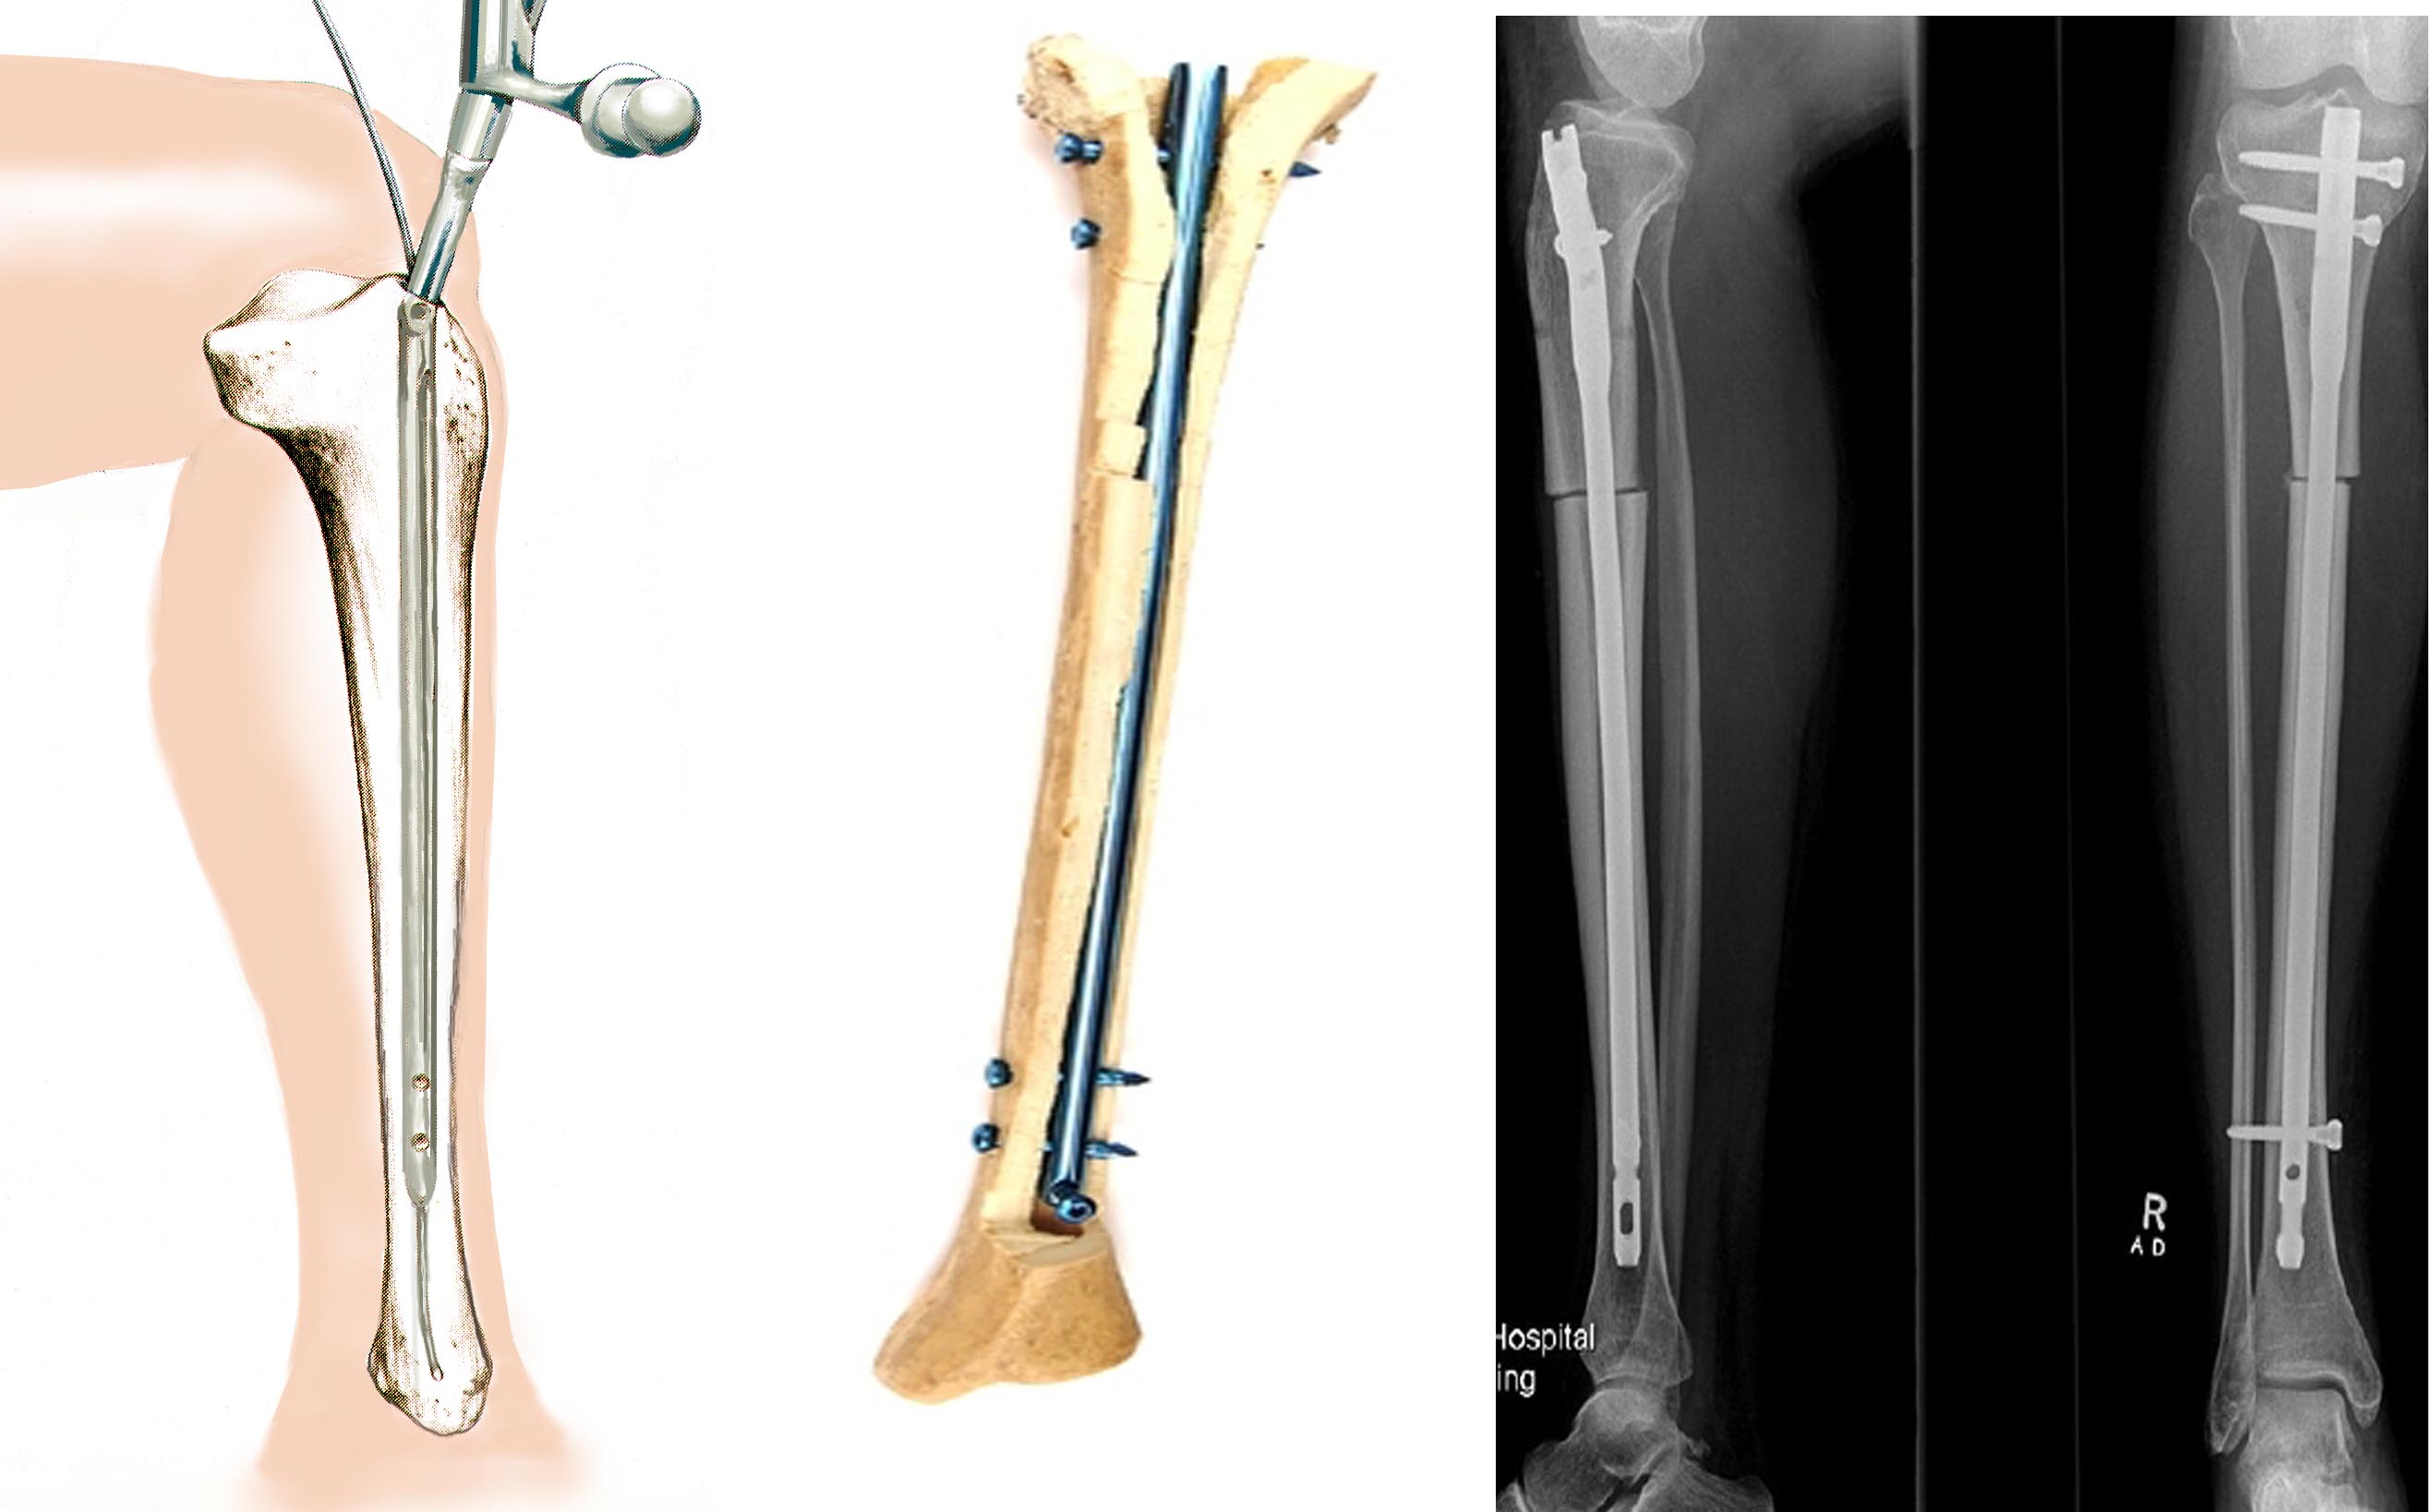

Компонент большеберцовый

Компонент большеберцовый 123 фотографий